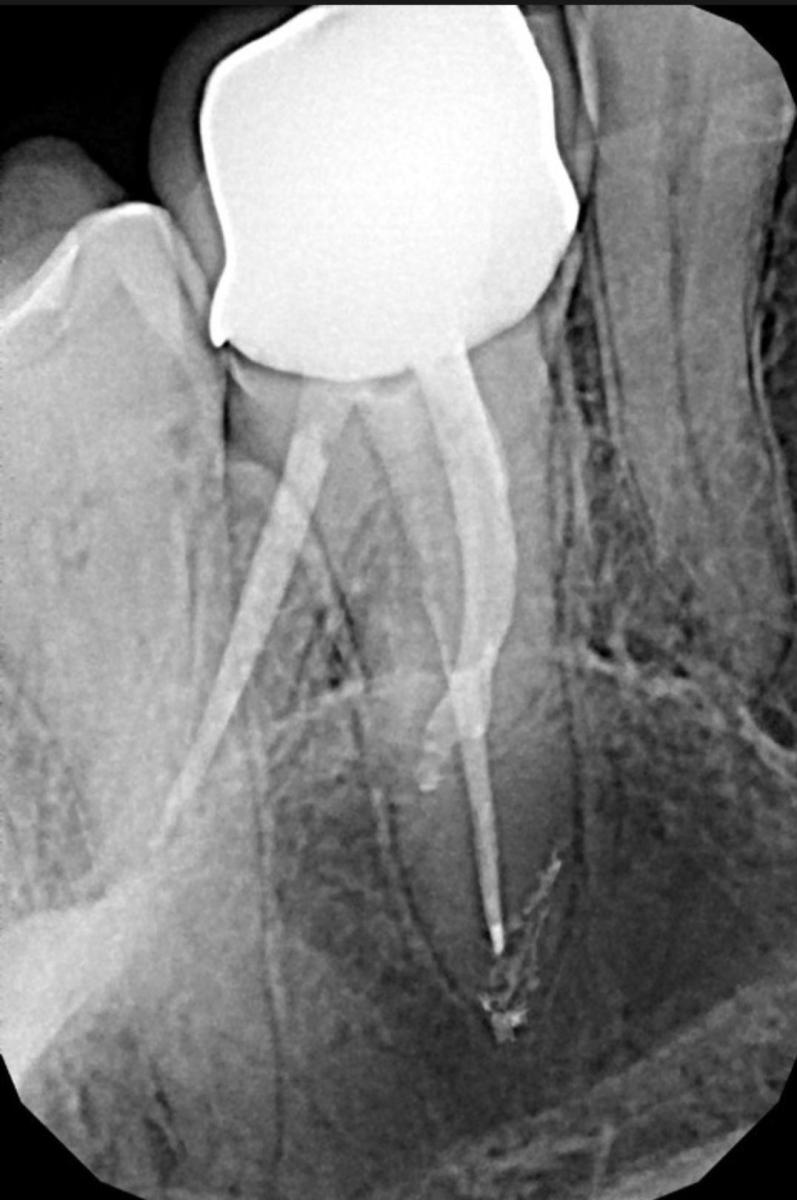

Коронку для корректировки цвета сняли и отправили на доработку. Оттиски второй раз не делали. После повторной установки спустя некоторое время стала воспаляться десна с небной стороны. Мною был сделан снимок для оценки состояния зуба. На снимке после корректировки (меняли только цвет как сказал специалист), часть конструкции с небной стороны изменилась.(сн.2) Граница соприкосновения не видна( вероятно керамика на снимке имеет схожую структуру с зубом.) Так как воспаляется и отслаивается десна именно в этом месте, возникает вопрос. Реально ли сделать второй раз идеальное прилегание без снятия слепков? Если корректировали по старым оттискам, зачем тогда переделывали, ведь получится первоначальный вариант?